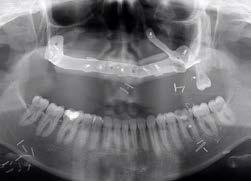

Panoramic view - severe posterior alveolar ridges atrophy

A follow-up panoramic X-ray was taken to evaluate osteointegration and bone-to-implant contact after three months

Demineralized freeze dried bone allograft covering the implant Postoperative panoramic view

Bone allograft placed over the implant A follow-up panoramic X-ray was taken to evaluate osteointegration and bone to-implant contact after three months

Post-op pano xray